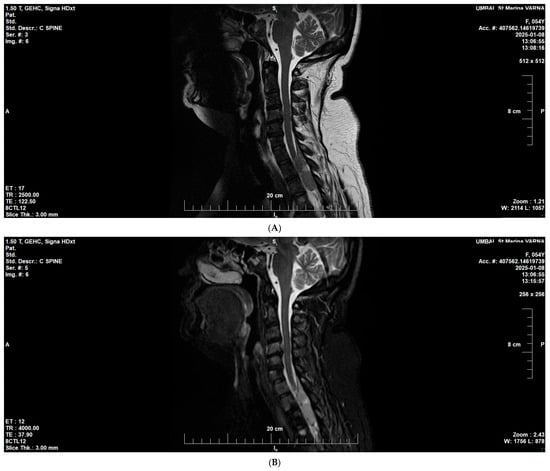

3.4. Bone Marrow and Spine Involvement in Multiple Myeloma